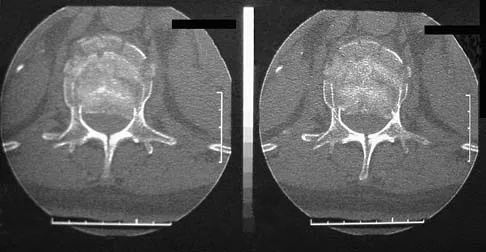

A right-handed 14-year-old pitcher has had a 3-month history of shoulder pain while pitching. Examination reveals full range of motion, a mildly positive impingement sign, pain with rotational movement, and no instability. Plain AP radiographs of both shoulders are shown in Figures 25a and 25b. Management should consist of

Correct Answer: rest until symptoms have resolved, followed by a gradual return to pitching.

Explanation:

The patient has the classic signs of Little Leaguer's shoulder, with findings that include pain localized to the proximal humerus during the act of throwing and radiographic evidence of widening of the proximal humeral physis. Examination usually reveals tenderness to palpation over the proximal humerus, but the presence of any swelling, weakness, atrophy, or loss of motion is unlikely. The treatment of choice is rest from throwing for at least 3 months, followed by a gradual return to pitching once the shoulder is asymptomatic. Carson WG Jr, Gasser SI: Little Leaguer's shoulder: A report of 23 cases. Am J Sports Med 1998;26:575-580.